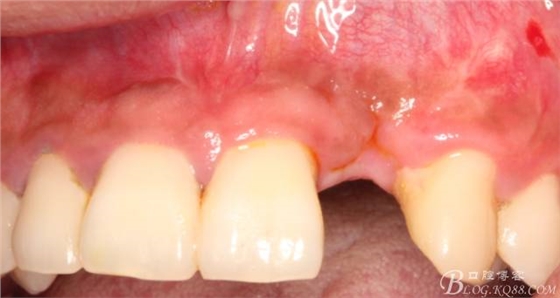

4個月后,唇側(cè)豐滿度尚可,與鄰牙之間齦乳頭完整。

保留齦乳頭翻小瓣。